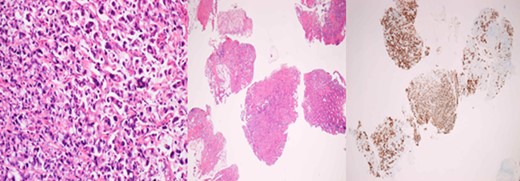

A 43-year-old female, 10 weeks postpartum, underwent colonoscopy for bleeding per rectum showing a bulky tumour (Fig. 1) in the rectum at 5 cm. Histologically poorly differentiated adenocarcinoma of the rectum (Fig. 2) T3N1Mo. Underwent laparoscopic loop ileostomy formation for impending bowel obstruction. Bloods showed Hemoglobin13.6 g/dL, Bilirubin 10umol/L, CEA 3.6 ng/mL. MRI pelvis (Fig. 3a and b) showed locally advanced annular neoplasm of mid and upper rectum. CT TAP (Fig. 4) reported no distant metastasis. She had neoadjuvant chemoradiothreapy with poor response. Post chemotherapy she noticed a lump in her right breast and axilla. Breast mammogram (Fig. 5a) showed 26 mm lesion in the right breast at 10 o'clock position and ultrasound showed 27 mm lesion in right axilla. Core biopsy (Fig. 6) reported signet ring morphology. The tumour stained positive with CK20, CDX-2 and CEA. There was no staining with CK7, ER, PR or Her-2. The rectal biopsy specimen, also analysed for KRAS status, was KRAS/NRAS/BRAF negative. She is being followed up by oncology with FOLFOX+Panitumumab.

Primary rectal biopsy showing mucinous poorly differentiated adenocarcinoma with signet cells KRAS/BRAS/NRAF negative.

Breast core biopsy showing features similar to the primary rectal cancer.